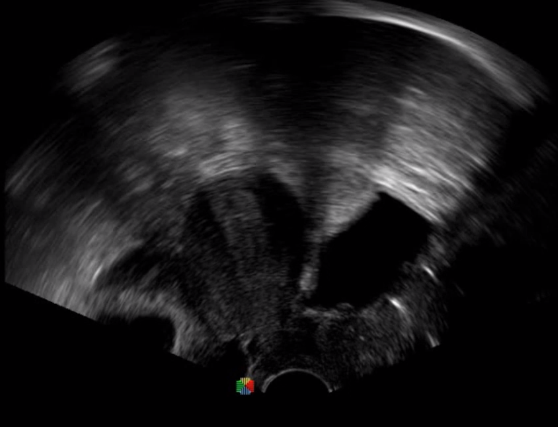

TEE(經(jīng)食道超聲心動圖)將超聲探頭置入食道內(nèi),從心臟的后方向前近距離探查其結(jié)構(gòu) ,克服了經(jīng)胸超聲檢查的局限性,避免肺內(nèi)氣體、胸壁脂肪、胸廓畸形等因素影響,觀察角度更多,圖像更加清晰,測量數(shù)據(jù)更準(zhǔn)確。

經(jīng)食道超聲 大動脈短軸